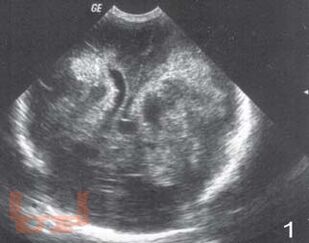

Монография посвящена вопросам ранней диагностики формирования тяжелых структурных постгипоксических изменений мозга у новорожденных детей с помощью определения в крови концентрации нейроспецифических белков, фактора роста сосудов, молекулы клеточной адгезии и маркера апоптоза в раннем периоде постнатальной адаптации. Перед педиатрами и неврологами, занимающимися новорожденными высокого риска всегда встает вопрос: разовьется ли у ребенка внутрижелудочковое кровоизлияние или перивентрикулярная лейкомаляция? Что лежит в основе таких изменений? Результаты, полученные в исследовании, позволили во многом расширить понимание патогенеза постгипоксических изменений головного мозга у новорожденных, а также выделить факторы, которые возможно применять в диагностике патологических процессов в ткани мозга как маркеры. Книга предназначена для детских неврологов, неонатологов, педиатров.